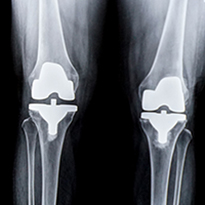

Joint Replacement Surgery

event-img-2.png